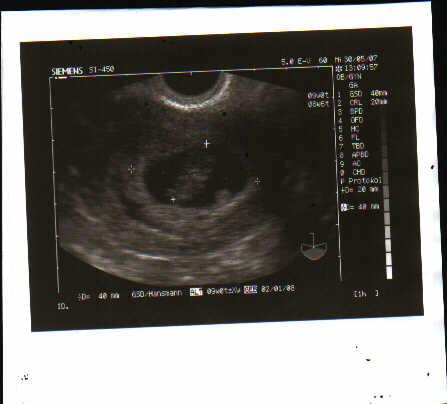

daher freu ich mich momentan über jeden mensfreien tag...aber mehr ist noch nicht drin...denn wer weiss ob die zwei tigerchen auch wirklich in der GM sitzen und es sich dort gemütlich gemacht haben???

ich sag dir ich geh bald am stock nun es sind noch 5 tage bis zum US